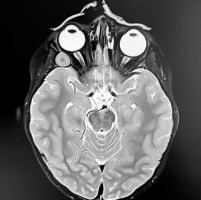

Examination revealed reduced visual acuity in the right eye (VOD) at 0.1 and intraocular pressure in both eyes measuring 7 mmHg. A physical examination of the right eye (OD) showed mixed ocular injection (Figure 1). Iris vascular dilation accompanied by posterior synechiae were observed. The cornea was hazy, and small punctate fluorescein-staining areas were observed in the lower hemisphere of its epithelium (likely resulting from the patient rubbing her painful eye). The lens was clear. Inflammatory cells were detected in the anterior chamber. The optical coherence tomography (OCT) scan of the macula was within normal limits. Due to limited visibility of the fundus, an ultrasound of the right eye was performed, revealing an oval hypoechoic mass in the orbit, measuring 17.95 mm × 11.35 mm. The lesion was located in the temporal region (Figure 2). Left eye (OS) examination revealed normal visual acuity, VOS 1.0. The anterior segment and fundus of the OS were within normal limits. For symptomatic management of anterior uveitis in the OD, topical dexamethasone and 1% tropicamide were administered, resulting in partial improvement. Due to significant anisometropia (refraction after 1% cyclopentolate-induced cycloplegia was +6.0 Dsph in the OD and +3.0 Dsph in the OS), the patient was prescribed spectacle correction (OD: +5.0 Dsph; OS: +2.0 Dsph). Ocular biometry revealed axial length discrepancy between OD (19.81 mm) and OS (21.18 mm).